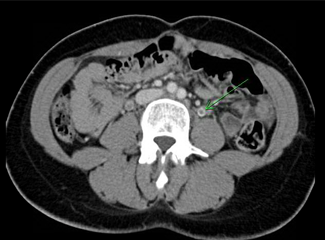

CT scans of the abdomen and pelvis (Figures 1-3) revealed bilateral ovarian vein thrombosis, worse on the right side than the left. A heparin infusion was immediately started to prevent a pulmonary embolism and therapy with broad-spectrum antibiotics (gentamicin and clindamycin) was also initiated.

Figure 2